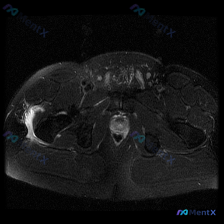

刚整理了一份骨盆MRI读片病例,分享一下分析思路,大家一起交流。 病例影像基本信息 这是一份骨盆水平的轴位T2加权MRI扫描,涵盖髋关节、股骨近端、盆腔底部及周边软组织结构,核心异常在右侧区域: 1. 核心异常发现:右侧股骨大转子外侧及前方,可见大片明显的T2高信号影,呈新月形/梭形包裹特征,位于股...